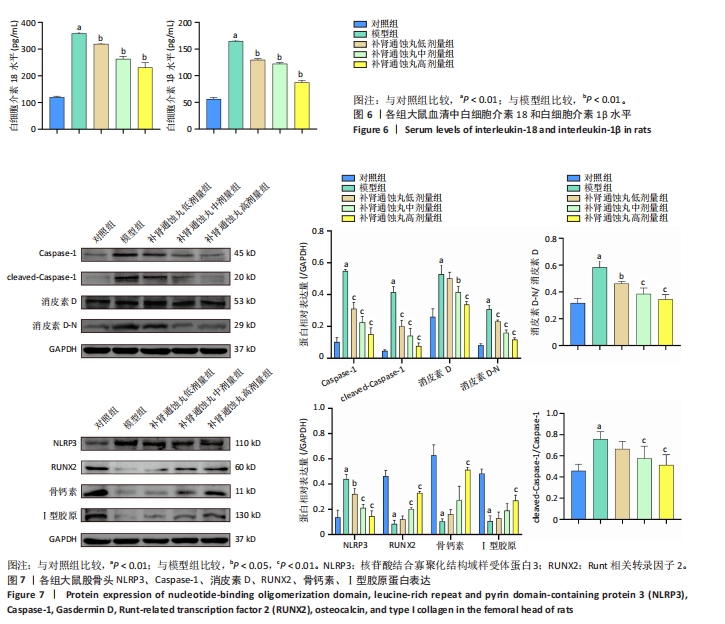

.1 实验动物数量分析 参加实验SD大鼠数量为50只,均进入结果分析。 2.2 Micro-CT检测结果 通过Micro-CT观察各组大鼠股骨头区域骨质变化,见图1。乙醇会导致大鼠股骨头软骨下骨骨量明显减少,骨小梁排列出现紊乱、稀疏等状况,而补肾通蚀丸能够改善上述情况,且呈现一定的剂量效应。模型组骨小梁厚度、骨小梁数目、骨体积分数、骨密度较对照组显著降低(P < 0.01),模型组骨小梁间隙较对照组则显著升高(P < 0.01)。经过不同剂量补肾通蚀丸干预后,各项指标均出现不同程度的逆向改变;其中,与模型组比较,补肾通蚀丸高剂量组骨小梁厚度、骨小梁数目、骨体积分数、骨密度均显著升高(P < 0.05),骨小梁间隙则显著降低(P < 0.05);与模型组比较,补肾通蚀丸中剂量组骨体积分数、骨密度显著升高(P < 0.05),骨小梁间隙则显著降低(P < 0.05);而补肾通蚀丸低剂量组仅在骨小梁间隙指标上较模型组显著降低(P < 0.05),见图2。 2.3 苏木精-伊红染色结果 与对照组比较,模型组大鼠股骨头出现核固缩现象,多见脂肪空泡,部分骨小梁出现断裂、变细;补肾通蚀丸低、中、高剂量组骨细胞核固缩和脂肪空泡较模型组有所减少;在整体结构方面,补肾通蚀丸低剂量组骨小梁变细现象较模型组未见明显改善,但断裂情况有所改善;而补肾通蚀丸中、高剂量组骨小梁断裂、变细情况较模型组均明显改善,见图3;在空骨陷窝率方面,模型组较对照组显著增高(P < 0.01);补肾通蚀丸中、高剂量组较模型组有所降低(P < 0.05),见图3。 2.4 免疫组化染色结果 与对照组比较,模型组NLRP3、Caspase-1、消皮素D蛋白表达明显增强,而Runt相关转录因子2、骨钙素、Ⅰ型胶原蛋白表达显著降低(P < 0.01);与模型组比较,补肾通蚀丸中、高剂量组能够显著降低NLRP3、Caspase-1、消皮素D蛋白表达,且促进Runt相关转录因子2、骨钙素、Ⅰ型胶原蛋白表达(P < 0.05),而补肾通蚀丸低剂量组骨钙素、Ⅰ型胶原蛋白表达有所上调(P < 0.05),其余指标则无明显差异(P > 0.05),见图4,5。 2.5 ELISA检测结果 与对照组比较,模型组大鼠血清中白细胞介素18和白细胞介素1β水平显著增高(P < 0.01);与模型组比较,补肾通蚀丸各剂量组大鼠血清中白细胞介素18和白细胞介素1β水平均显著降低(P < 0.01),且以一定剂量依赖方式递减,见图6。 2.6 Western blot检测结果 与对照组比较,模型组大鼠股骨头组织中NLRP3、cleaved-Caspase-1、Caspase-1、消皮素D、消皮"

素D-N蛋白表达均显著上调(P < 0.01),成骨因子Runt相关转录因子2、骨钙素、Ⅰ型胶原蛋白表达均显著下调(P < 0.05);补肾通蚀丸各剂量组NLRP3、cleaved-Caspase-1、Caspase-1、消皮素D、消皮素D-N蛋白表达以一定剂量依赖方式呈现不同程度的下调,Runt相关转录因子2、骨钙素、Ⅰ型胶原蛋白表达则以一定剂量依赖方式呈现不同程度的上调;与模型组比较,补肾通蚀丸中、高剂量组NLRP3、cleaved-Caspase-1、Caspase-1、消皮素D、消皮素D-N蛋白表达均显著下调(P < 0.05),补肾通蚀丸高剂量组Runt相关转录因子2、骨钙素、Ⅰ型胶原表达均显著上调(P < 0.01),补肾通蚀丸中剂量组Runt相关转录因子2蛋白表达显著上调,而骨钙素、Ⅰ型胶原表达无明显差异(P > 0.05),补肾通蚀丸低剂量组Runt相关转录因子2、骨钙素、Ⅰ型胶原表达均无明显差异(P > 0.05),见图7A,B。与对照组比较,模型组cleaved-Caspase-1/Caspase-1比值和消皮素D-N/消皮素D比值均显著上升(P < 0.01);与模型组比较,补肾通蚀丸中、高剂量组cleaved-Caspase-1/Caspase-1比值和消皮素D-N/消皮素D比值均显著下降(P < 0.01),而补肾通蚀丸低剂量组cleaved-Caspase-1/Caspase-1比值与对照组比较无明显差异(P > 0.05),见图7C。 2.7 RT-qPCR检测结果 RT-qPCR结果显示,与对照组比较,模型组大鼠股骨头组织中NLRP3、Caspase-1、消皮素D mRNA表达显著上调,Runt相关转录因子2、骨钙素、Ⅰ型胶原mRNA表达显著下调(P < 0.01);与模型组比较,补肾通蚀丸中、高剂量组NLRP3、Caspase-1、消皮素D mRNA表达均显著下调,Runt相关转录因子2、骨钙素、Ⅰ型胶原mRNA表达均显著上调(P < 0.01),而补肾通蚀丸低剂量组NLRP3、Caspase-1、Runt相关转录因子2、骨钙素mRNA表达均无明显差异(P > 0.05),见图8。"